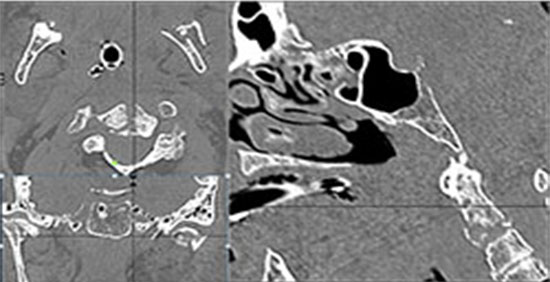

Right Temporal Bone

Left Temporal Bone

The ossicles, in particular the incus long process, the incudostapedial joint and stapes are fractured or dislocated.

The facial canal including the labyrinthine, tympanic and descending portions and nerve are fractured.

The inner ear including the lateral semicircular canals, vestibule and/or cochlea is fractured or otherwise abnormal.